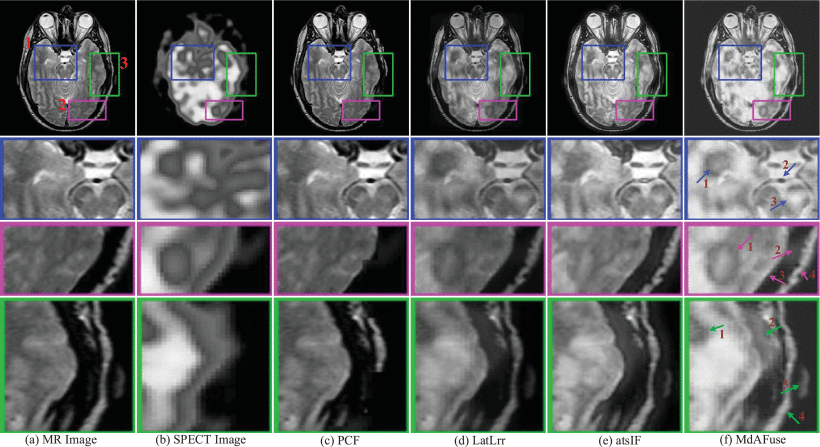

Evaluation: In the fusion experiment of the following two figures, the test data were MR and SPECT brain images with glioma, which is a typical application in the brain nervous system. They are identified in the test dataset and respectively correspond to No. 010 and No. 029. Fusion of MRI and PET/SPECT can integrate biological anatomical information and physiological metabolic information, which can help doctors to locate and diagnose lesions. Several existing fusion algorithms based on traditional and deep learning methods are analyzed and compared.

Results: Three kinds of traditional fusion methods are tested and compared with the MdAFuse model. As illustrated in the first figure below, the first column and second column display the MR and SPECT source images, respectively, from some cases with brain abnormalities. The following columns show the results obtained by three traditional methods and MdAFuse, with one column for each method. In the same figures, we can observe the differences among the fused images from different fusion methods. PCF is a fusion method using wavelet transform, and the fused image has serious information loss. LatLrr is a low-rank representation method, and its fusion strategy is simple weighted average. The results of this method can maintain good texture details but less SPECT image information. atsIF (adaptive dual scale image fusion) [Ext. Ref.] is a fusion strategy through color space conversion, which can retain more SPECT information, but MR details are lost. Compared with other methods, MdAFuse can better preserve the information of the two source images. In the first line, three corresponding parts of each image inside three colorful squares are enlarged and shown in the 2nd, 3rd and 4th lines for clearer comparison.

The second line in the first figure below lists the enlarged images corresponding to the parts inside blue squares in the first line. In the last column, we mark three arrows pointing to the temporal lobe, basilar artery and pontine. The temporal lobe is gray and irregular in the MR image. SPECT shows a lighter gray circle with an obvious color difference. In the PCF results, the area is not obvious, and the features are completely retained on MR but not on SPECT. In the results of LatLrr fusion, the area can retain the information of the two source images but also loses part of the SPECT information, such as the pixel value around the temporal lobe, which is not different. The effect of the atsIF method is greatly improved in terms of brightness, which can retain more information in SPECT, but information loss occurs with the combined source image. Compared with other methods, MdAFuse can perfectly preserve the features of the temporal lobe region. For the basilar artery area, an obvious difference is also noted. In the MR image, the area is a small black ellipse, while in SPECT, it is an even gray area without shape features. PCF completely retains the information on MRI, LatLrr and MdAFuse show a dark gray color for this position area, and the shape is not changed. The fusion result of atsIF becomes a white area, and a black circle is evident outside the small ellipse. Arrow 3 points to the pontine area, which is an area with an uneven gray distribution on MR images and a small area with obvious brightness similar to triangle on SPECT images. Similarly, the feature information of SPECT cannot be found in the fusion results of PCF, and the brightness information of this location area is not obvious in the LatLrr and atsIF results. The features of MR and SPECT can be clearly viewed in the results of this method.

The third line in the first figure below lists the enlarged images corresponding to the parts inside purple squares in the first line. Similarly, in the last column, we mark four arrows pointing to the occipital lobe, occipital bone, lateral sinus and occipital lobe contour. From the display of the four arrows, it also proves that the fusion result of MdAFuse is better especially in the area of first arrow. The fourth line lists the enlarged images corresponding to the parts inside blue squares in the first line. The four arrows in the last column point to the temporal lobe, temporal muscle, pinna and lateral occipital bone. From the display of the four arrows, it also proves that the fusion result of MdAFuse is better.

Fused results and their enlarged ROIs of the same pair of MR-SPECT images by some traditional fusion methods (PCF [Ext. Ref.], LatLrr [Ext. Ref.], atsIF [Ext. Ref.]) and the proposed fusion method (dataset No. 010)